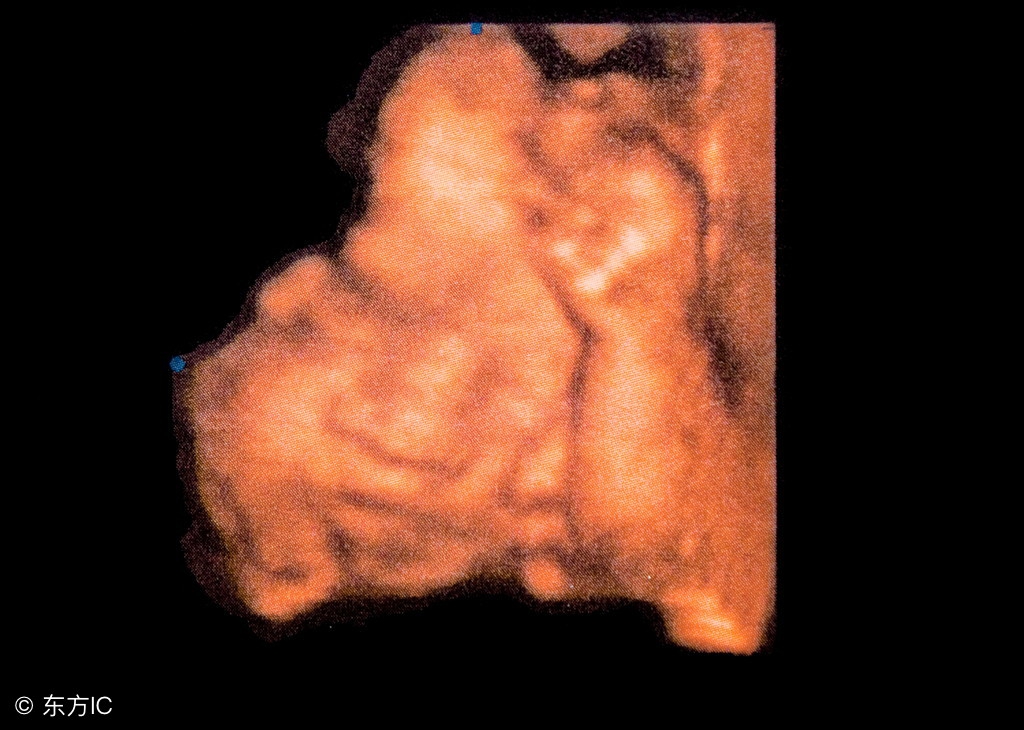

20周过后,随着宝宝的长大,胎动也会越来越明显,宝妈可以明显感觉到宝宝在妈妈肚子里拳打脚踢的感觉,28周至38周是胎动最为明显的时期,宝妈可以仔细观察,一般一小时胎动在3-5次为正常,12小时胎动次数在30至40次。宝宝38周以后,由于宝宝过大,妈妈的子宫这个小房子对宝宝而言显得太小了,胎动会稍减少。